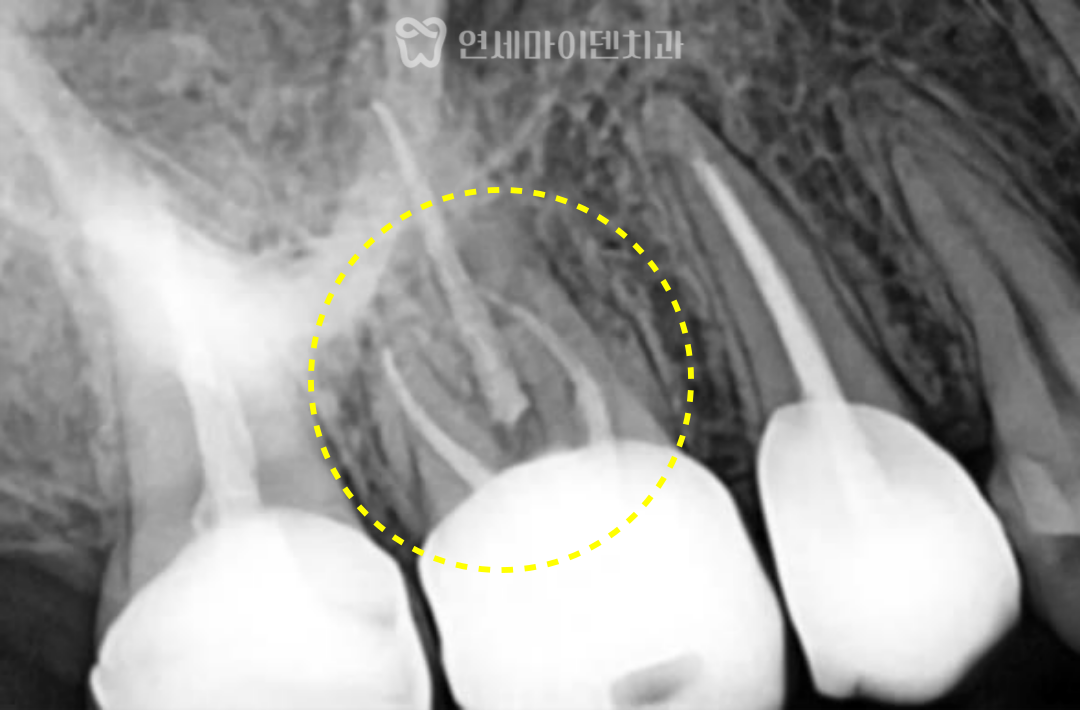

#16번 어금니 재신경치료 – CT를 통해 놓쳐진 ‘MB2 신경관’ 발견

이번 소개해드릴 어금니도 마찬가지로

신경관 하나가 놓쳐진 상태였습니다.

다만 CT 영상을 통해 놓치기 쉬운

‘MB2 신경관’을 발견할 수 있었고,

해당 신경관을 포함해

전체적인 재신경치료를 계획하게 되었습니다.